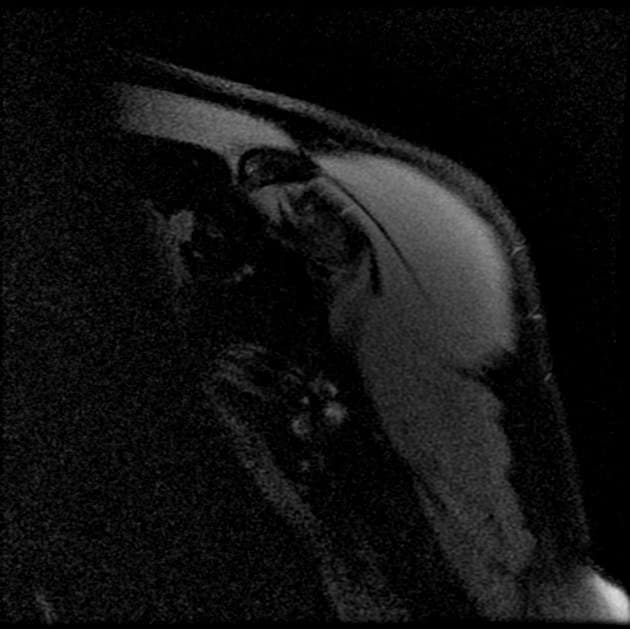

Chỏm xương cánh tay trái bị trật khớp ra trước và xuống dưới. Hình ảnh dẹt phần sau chỏm xương cánh tay gợi ý tổn thương Hill-Sachs. So sánh với phim X-quang đã thực hiện trước đó trong ngày. Chỏm xương cánh tay trái trật khớp ra trước và xuống dưới trước đó hiện đã được nắn chỉnh. Có tổn thương Hill-Sachs. Không thấy hình ảnh gãy xương Bankart.

Trật khớp vai ra trước kèm tổn thương Hill-Sachs

- "Tổn thương Hill-Sachs là một vết gãy do nén ở phần sau ngoài của chỏm xương cánh tay."

- "Tổn thương Hill-Sachs là một gãy xương do nén ở phần sau ngoài của chỏm xương cánh tay."

- "Nó xảy ra khi chỏm xương cánh tay bị ép vào bờ trước ổ chảo trong quá trình trật khớp."